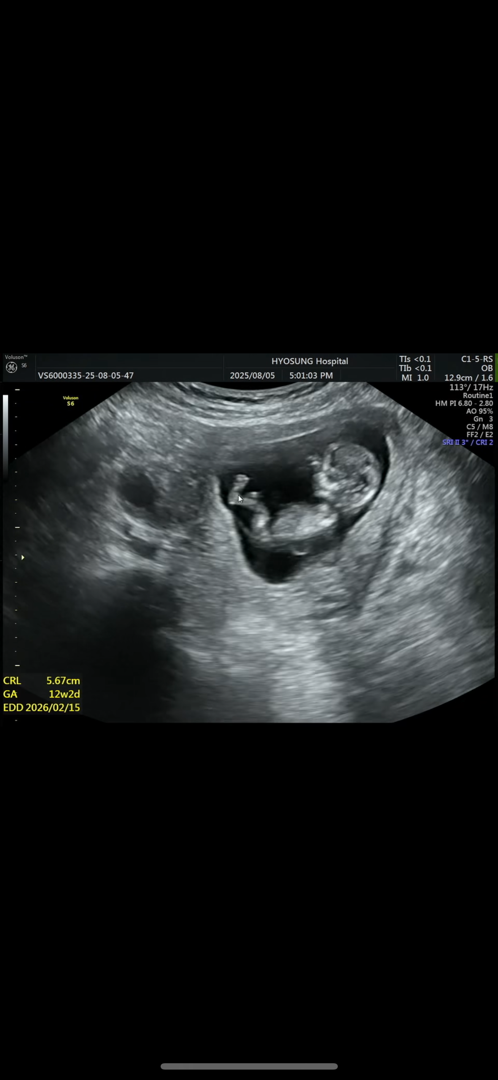

11주2일차 각도법 한번만 봐주세여ㅠㅠ

아들일까요 딸일까요ㅠㅠ 첫찌는 아들인데^^,,, 둘째는 딸 바라고 잇어요 🥺

생식기가 안 보이는 거 같아용!!

안 보여서 구분이 어려워용 ㅠㅠㅠ 생식기가 보여야 각도법 예측할 수 있어요!